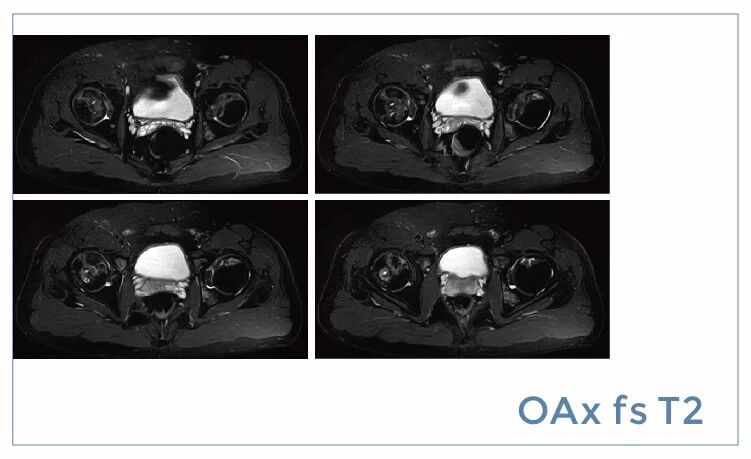

【朗润影像档案】20190719磁共振影像病例结果讨论